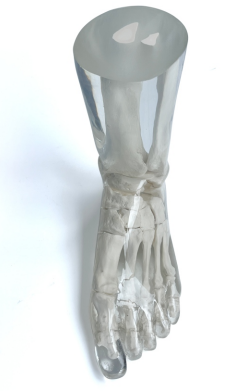

成人腿部模體,用于 X 射線 CT 和超聲波的成人腿部(肌肉)模型是一種基于人類男性腿部平均解剖結(jié)構(gòu)設(shè)計(jì)的逼真模型。它具有所有基本的骨骼和

軟組織特征,使其成為學(xué)習(xí)、研究和測(cè)試醫(yī)學(xué)成像設(shè)備的理想工具。 模體可用于研究不同方向和定位技術(shù)的多種診斷性 X 射線 CT 和超聲程序。根據(jù)

要求,該產(chǎn)品可以根據(jù)不同的病理進(jìn)行定制,也可以用于特定的培訓(xùn)應(yīng)用。 模體尺寸:965.2 x 254 x 177.8 毫米,重量:12kg(約)